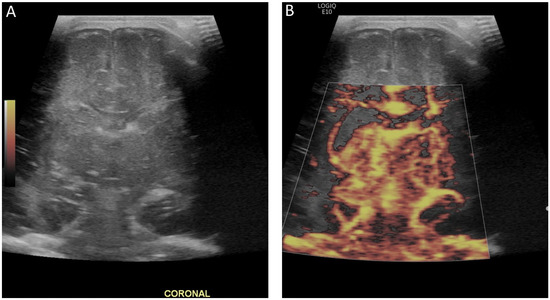

Figure 5.

(A) Ultrasound with color microvascular imaging in a 6 day old, former 32 week 2 day infant with multiple congenital anomalies including absence of the septum pellucidum. Overall reduced cortical and deep gray nuclei microvascular flow is observed. (B) Ultrasound with color microvascular imaging of a 51 day old, former term infant with congenital hydrocephalus. Overall increased microvascular perfusion is seen throughout the cortex, white matter, and deep gray matter compared to the infant in (A). The significance of these and similar findings has yet to be elucidated and may be of import for clinical management and prognostication.

Figure 6.

(A) Grayscale and (B) color microvascular imaging ultrasound a 13 day old, former 33 week 5 day infant with congenital heart disease and hypoxic respiratory failure on extracorporeal membrane oxygenation with seizures. Elevated flow is seen within the deep gray matter. This may reflect perfusion alterations in the setting of seizure, dysfunctional autoregulation, and/or evolving injury.